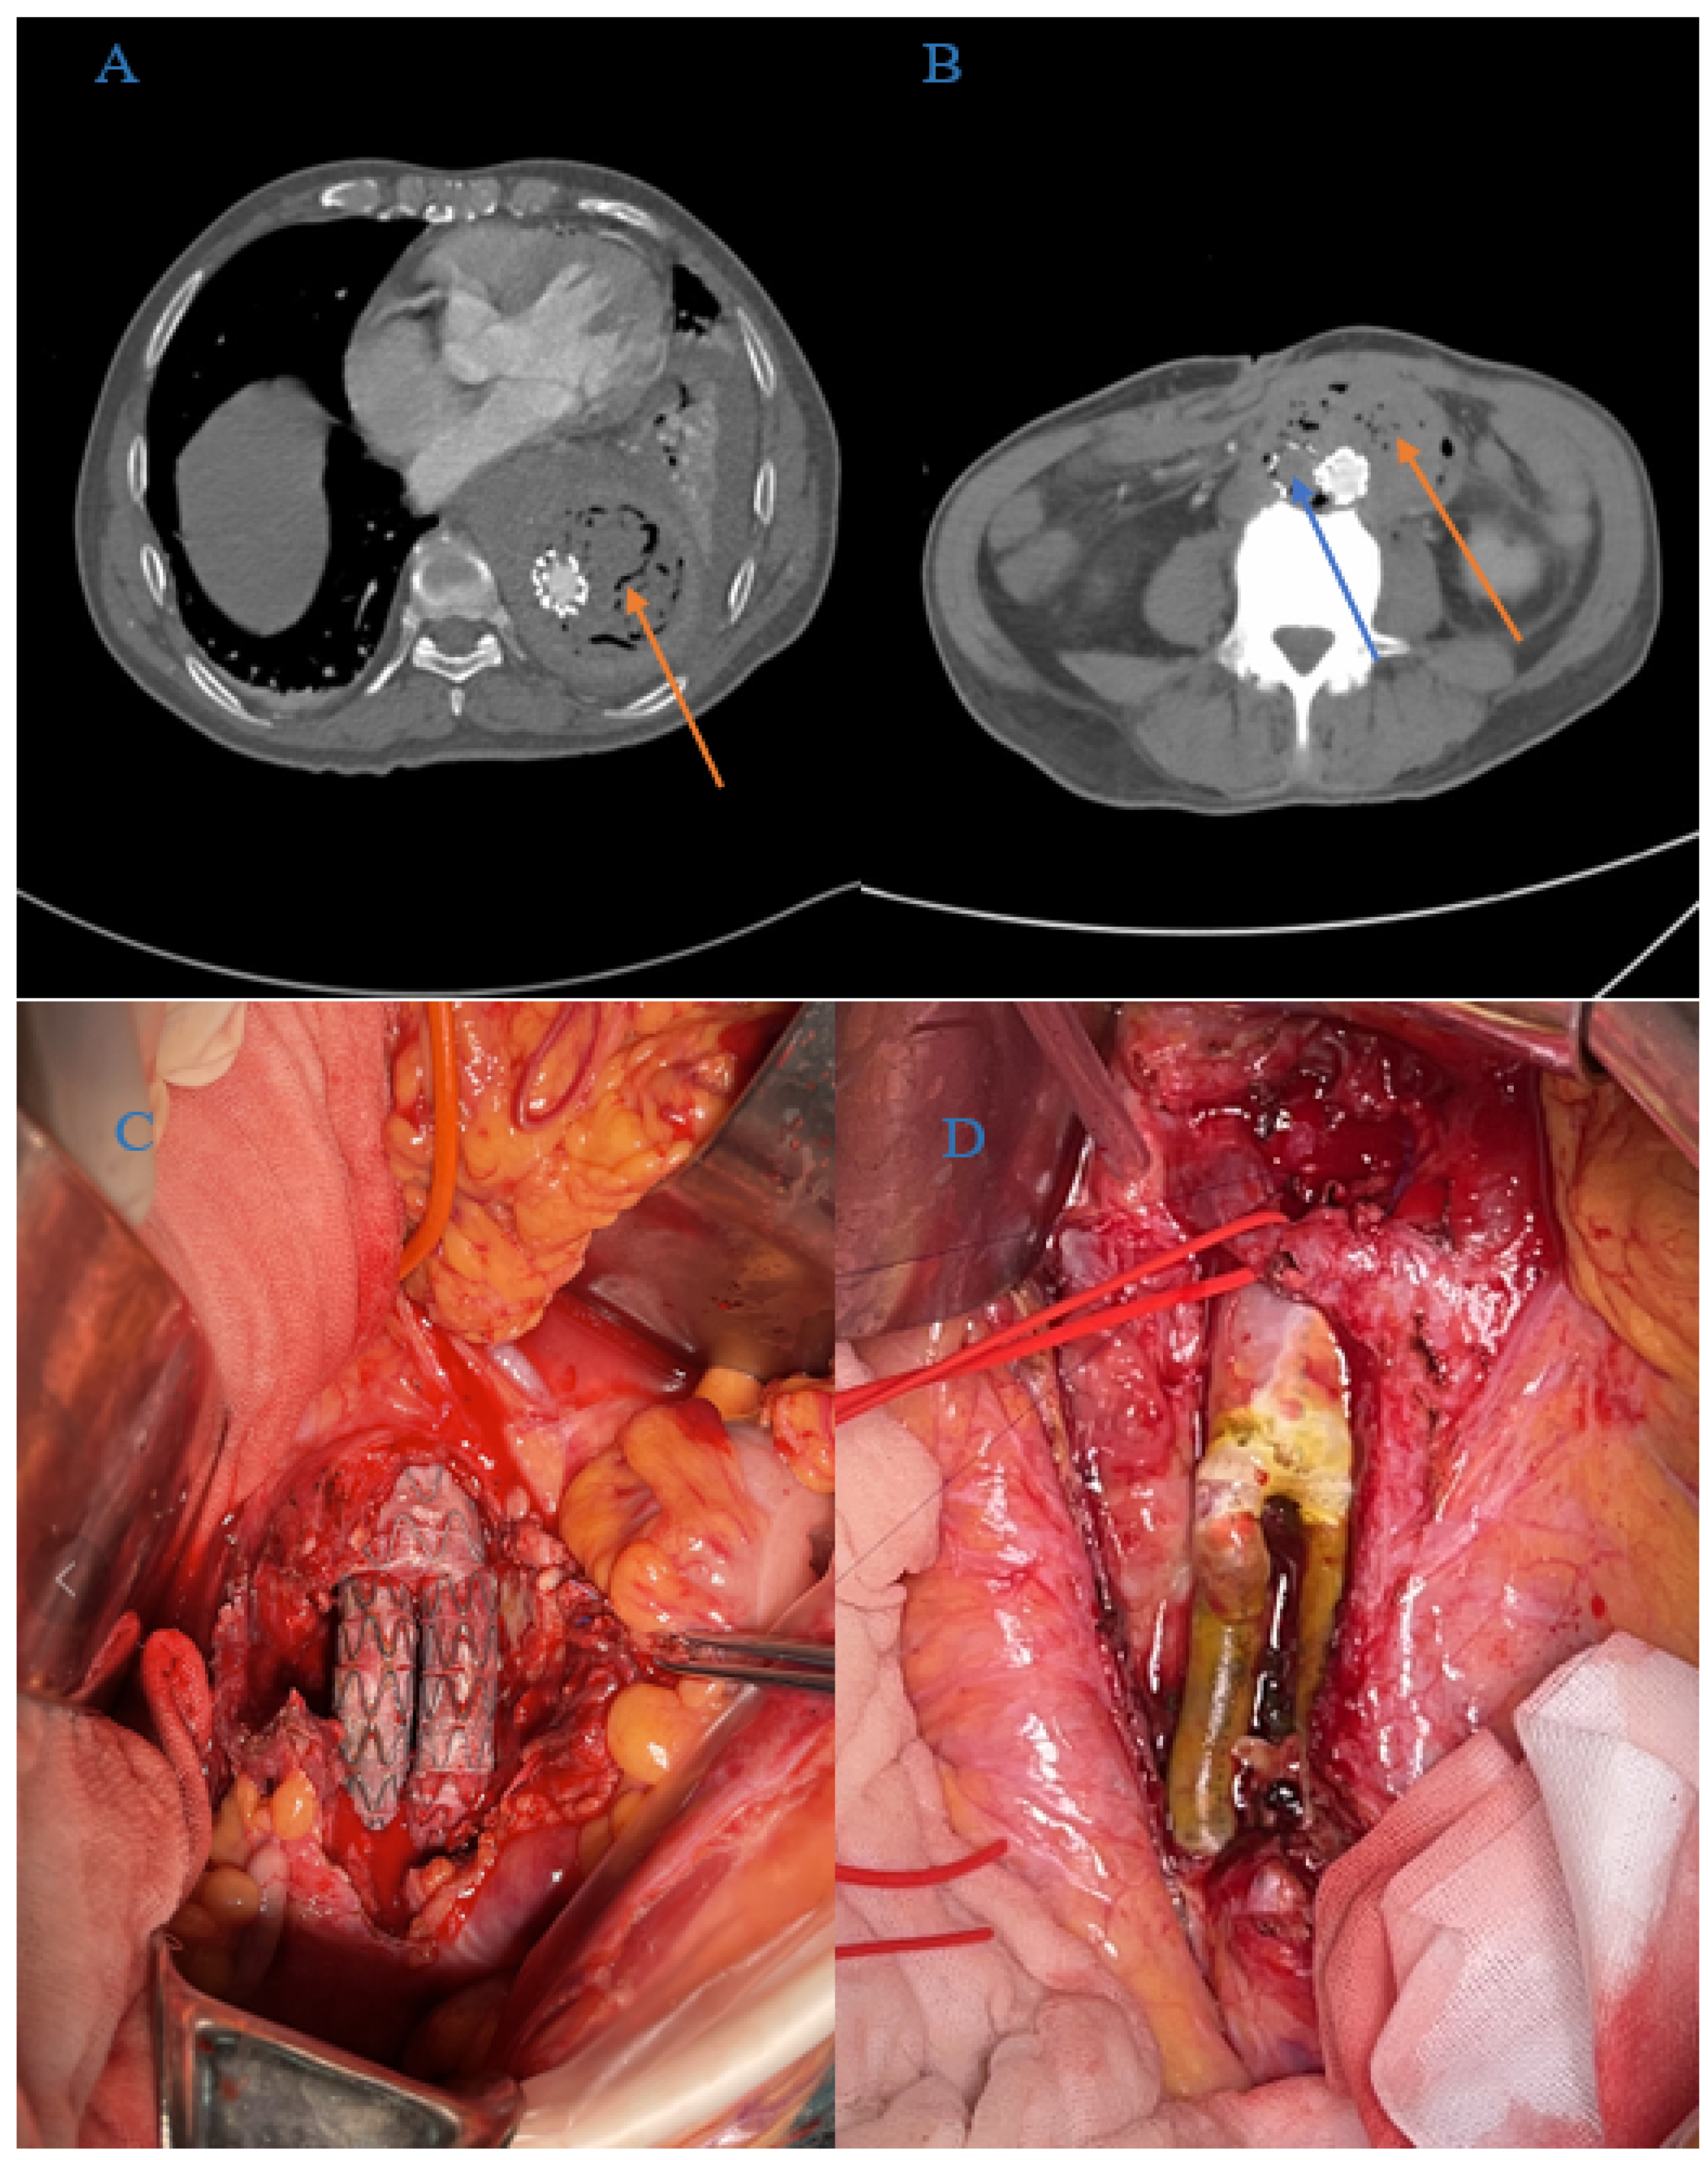

From January 2008 to December 2019, 43 patients with AGI were admitted to our department (median age, 70 years; interquartile range, 57–78 years); their medical records were retrospectively collected from the hospital database for statistical analysis (see Figure 1). AGI was diagnosed based on clinical symptoms (fever, abdominal or back pain, gastrointestinal bleeding, dyspnea or hypoxemia, and so forth) and auxiliary examination results (radiography, ultrasonography, and CT angiography), which indicated the presence of peri-graft gas or fluid, retroperitoneal abscess, graft duodenal fistula, pseudoaneurysms, and graft thrombosis (see Figure 2A,B).

Figure 2.

Peri-operative images of AGI patients. (A) Pre-operative CTA image of an AGI patient who previously underwent TEVAR (the orange arrow indicates the peri-graft fluid and gas). (B) Pre-operative CTA image of an AGI who underwent EVAR prior to AGI (orange and blue arrow indicate the peri-graft fluid and gas and graft thrombosis, respectively). (C) Peri-operative image of the ISR procedure. (D) Autologous vein was used as bypass graft conduits in ISR procedures.